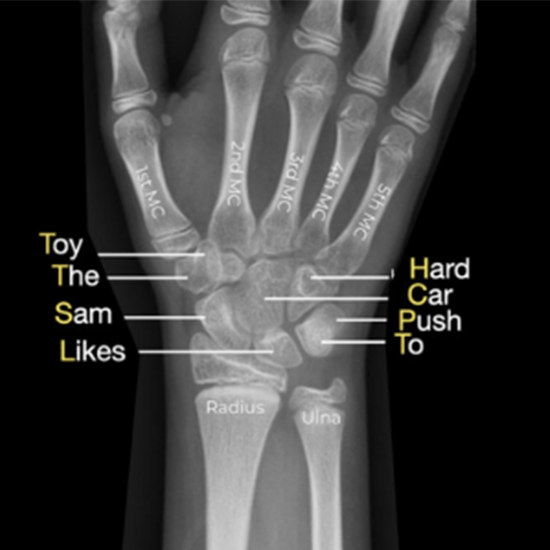

AP X-Ray Wrist Viewing assists in visualizing the wrist. The wrist is formed by the forearm bones (radius and ulna) and eight tiny wrist bones (carpal bones). It is advised in the event of foot symptoms such as pain, soreness, and swelling.

For the AP (Antero-Posterior) view, the patient is positioned in front of the X-ray beam.